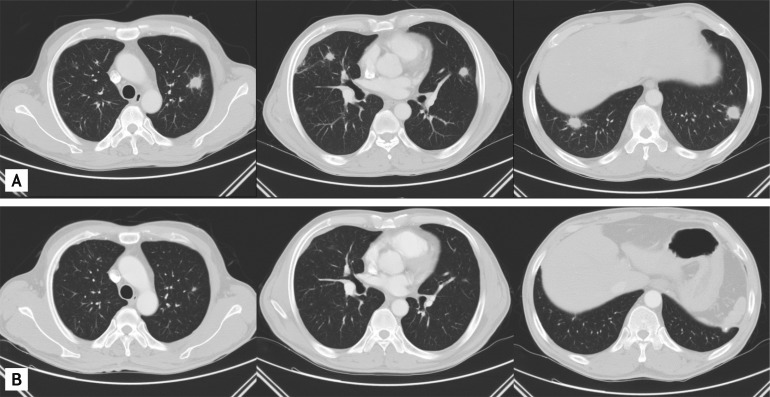

The standardized uptake values of the pulmonary nodules were from 4.37 to 5.59, strongly suggesting a malignancy (Fig. 2). A pulmonary malignancy was suspected and percutaneous needle aspirations of the pulmonary nodules and inguinal lymph nodes were performed. The cytopathological examination showed only many neutrophils and lymphocytes.

Figure 2

Positron emission tomography and computed tomography scans showed increased fluorodeoxyglucose activity in multiple pulmonary nodules.